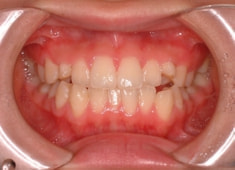

先天欠如歯両側上顎3番

治療前

治療開始時